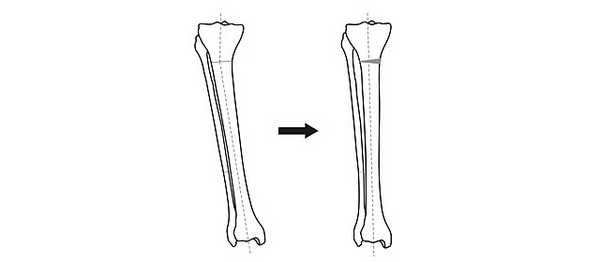

Общий принцип коррекции формы ног - пересечение кости в области деформации и сращение в правильном положении.

Схема исправления оси большеберцовой кости

Для выполнения остеотомии вовсе не обязательно делать большой разрез кожи. Достаточно небольшого (5 мм) прокола и наложения одного шва. При эстетически благоприятном распределении мягких тканей на голени отличного результата можно добиться, не пересекая кость полностью, а лишь надламывая её с одной стороны. Это позволяет рассчитывать на сокращение сроков лечения на 5-15%.

После пересечения кости (остеотомии) необходимо вывести ось конечности в правильное положение и зафиксировать в этом положении до сращения.